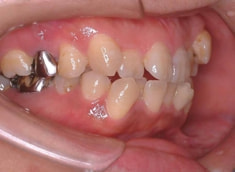

治療後(2年5ヶ月後)